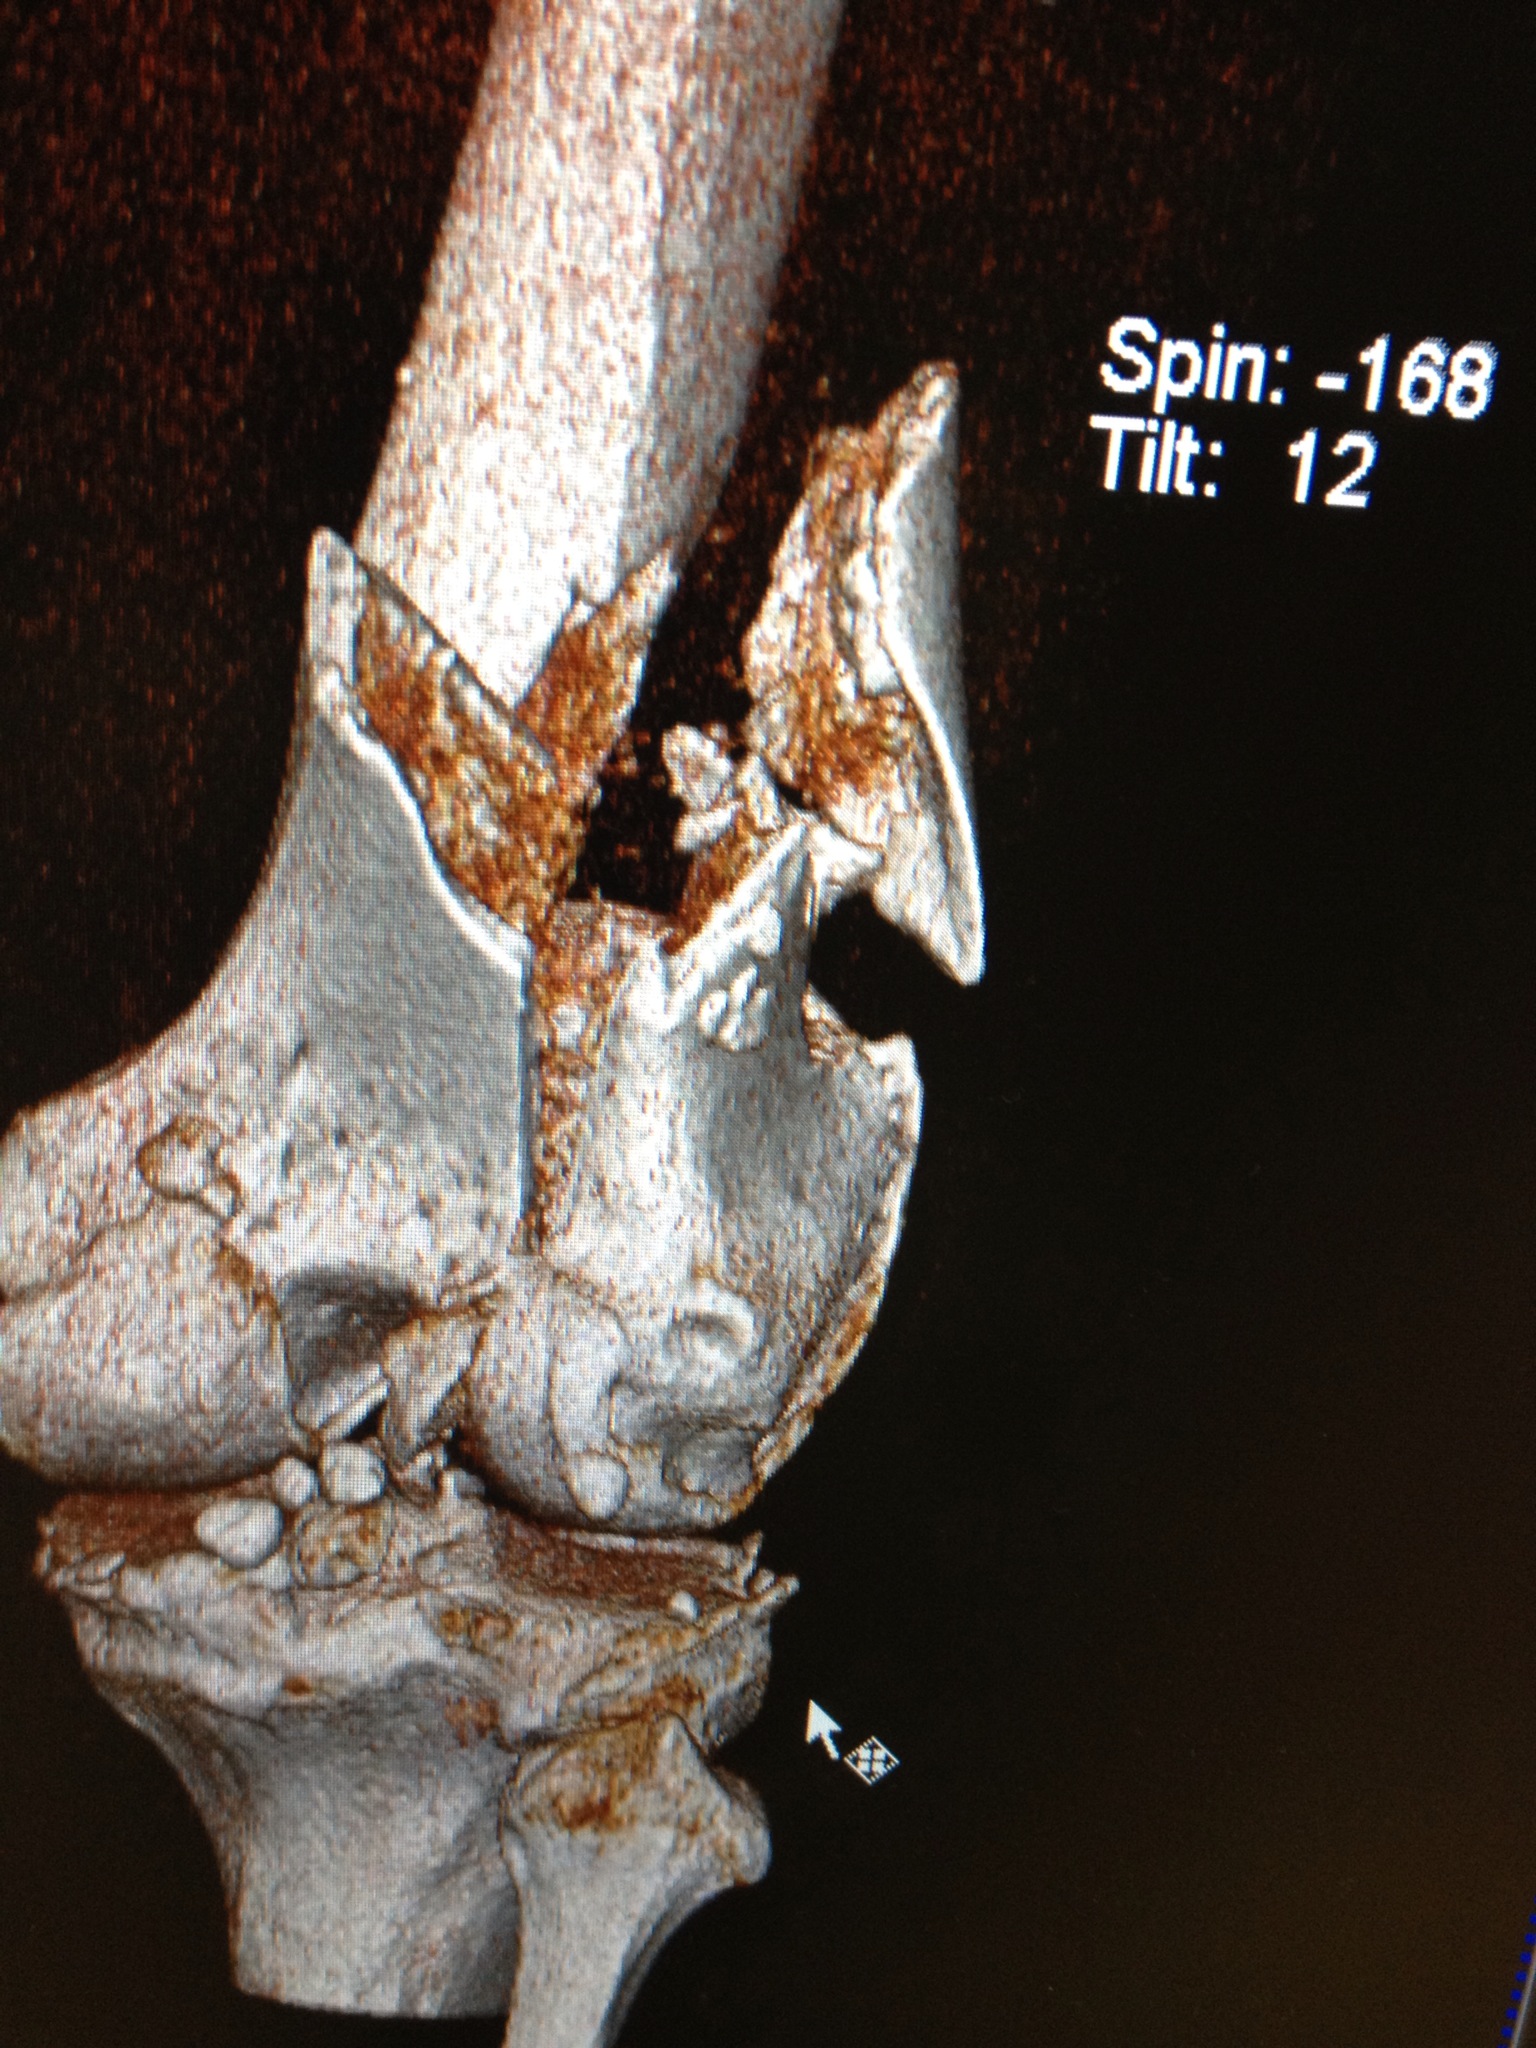

La artroscopia de rodilla es un procedimiento de mínima invasión en el que se hacen dos pequeñas incisiones de 4 mm a cada lado de la rodilla. Este método nos permite reparar lesiones de meniscos, que es la patología más común en larodilla; lesiones ligamentarias, lesiones del cartílago articular. Es útil también como método auxiliar en algunos procedimientos combinados en donde se utiliza cirugía convencional para fracturas y con control artroscópico se cuida que la articulación quede en óptimas condiciones.

Actualmente la lesión de Ligamento Cruzado Anterior (LCA) ya no implica un problema su reparación y aún en deportistas de alto rendimiento pueden retornar a su alto nivel deportivo. La cirugía sin embargo, requiere de alta precisión para su éxito, por lo que requiere de una alta experiencia por parte del cirujano ortopedista. El procedimiento se realiza por tres incisiones, dos de 4 mm y una de 1 a 2.5 cm, por una de las incisiones menores se introduce la cámara con la que se revisa toda la articulación, por otra de las pequeñas incisiones se introducen los instrumentos necesarios y por la tercera se obtiene y se tuneliza el nuevo ligamento.